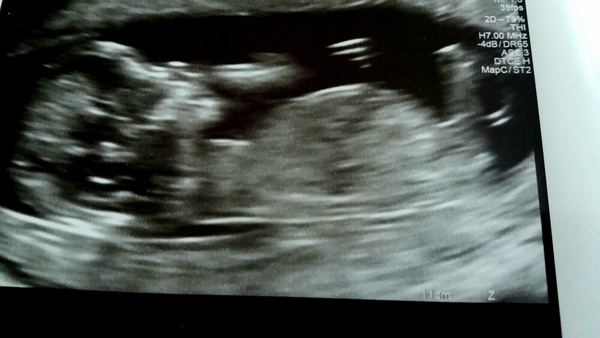

Lovely scan today. Baby was super active and poor sonographer had to spend ages trying to do the measurements. I'm measured at 13 weeks so official due date is 26th October now. Can I stay in the group?!